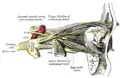

Намёт мозжечка. Вид сверху. Нервы орбиты, ресничный узел. Вид сбоку.

Нервы орбиты, ресничный узел. Вид сбоку. Внутренняя сонная артерия.